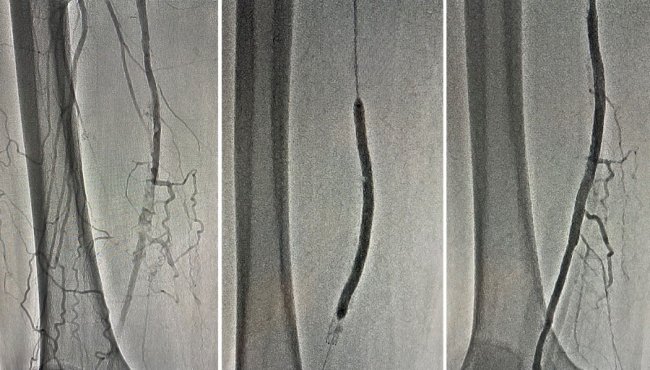

Після проведення ангіографії нижніх кінцівок діагностовано субоклюзію та оклюзію дистальних відділів поверхневих стегнових артерій - 100% і 98%. Команда ендоваскулярних хірургів провела стентування обох артерій через проколи в паху.

Операція пройшла успішно. Лікарям вдалося повністю відновити кровотік в судинах та запобігти втраті обох кінцівок. Нині біль в ногах пацієнта не турбує. На третій день після операції його виписали з лікарні.